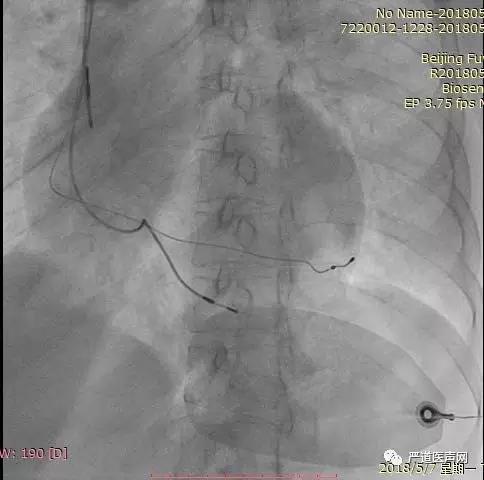

行锁骨下静脉穿刺,将美敦力带止血阀新型左室递送系统送入右房,用EP导管找到冠状窦口,经EP导管指引,将左室传送鞘管送入冠状窦。随后移除EP导管,直接通过递送鞘管进行造影,未发现侧静脉。再缓慢后撤传送鞘管至冠状窦口后,再次进行造影显示侧静脉开口,显影完全,最后植入美敦力4298左室四极电极。

术中通过左室电极递送鞘管寻找侧静脉

术后影像

新型的左室递送系统能简化手术流程,提高手术成功率。四极电极因有多种起搏向量选择,可选择固定良好的血管,同时简化术后左室阀值测试流程,日后新型的左室递送系统、四极电极必将成为CRT植入术的发展趋势。随着技术的不断改进,临床上普遍认为技术难度较高的CRT植入技术也会成为更加简单的技术。